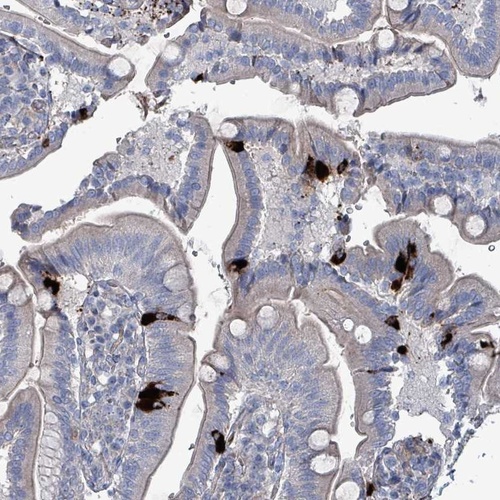

Immunohistochemical staining of human duodenum shows strong cytoplasmic positivity in enteroendocrine cells.